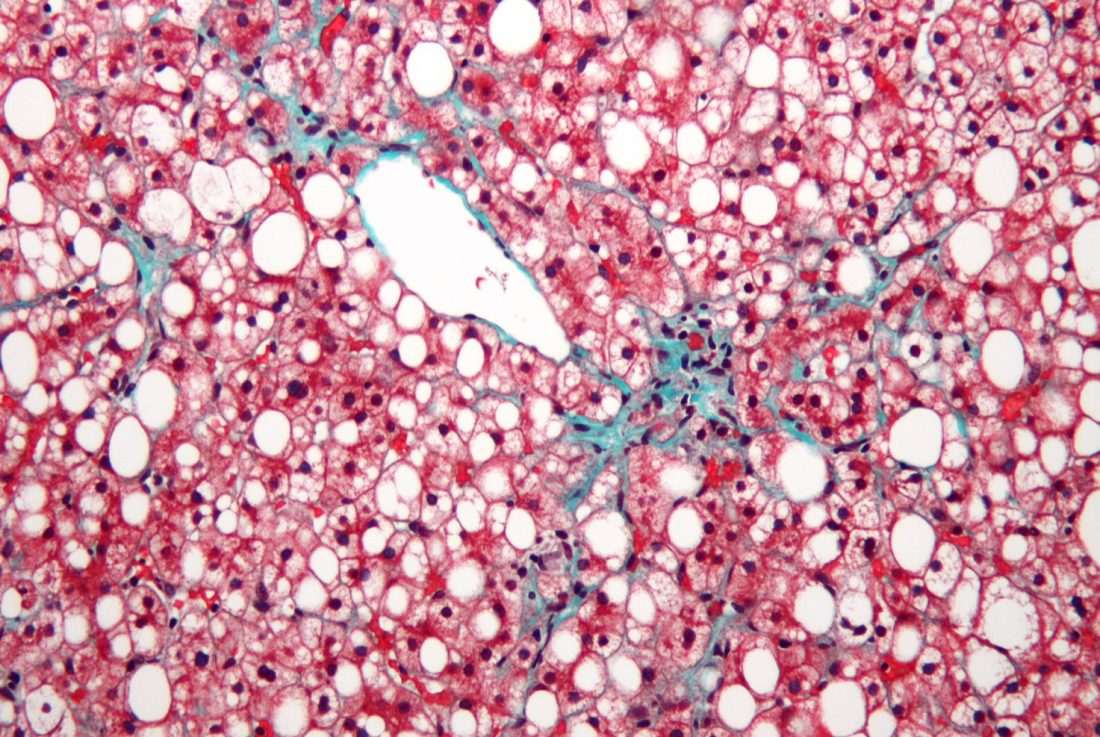

Organovo与Viscient Biosciences合作进行用于肝病治疗的3D打印研究